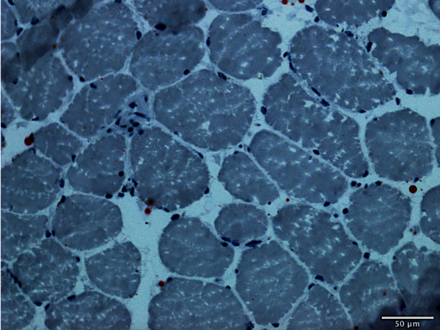

Histologie

L’histologie est l’étude des tissus biologiques au microscope, souvent à l’aide de colorations spécifiques qui permettent d’observer la structure des cellules et des tissus.